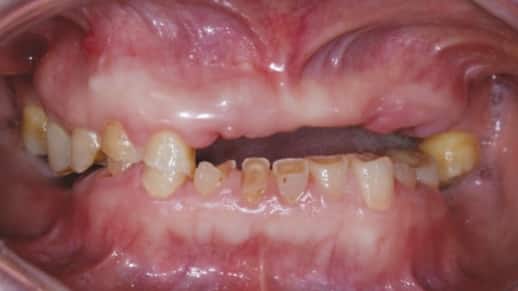

Разрушение зубов, известное как кариес, затрагивает значительную часть населения нашей планеты. Кариозные изменения возникают при наличии двух ключевых факторов:

Бактерии всегда присутствуют в полости рта, однако их разрушительное влияние сдерживается слюной. Если рацион человека содержит много углеводов или имеются заболевания органов пищеварения, состав слюны может изменяться, что приводит к снижению ее защитных свойств. В результате начинается процесс разрушения зубов.

Как избавиться от кариеса? Лечение проводит стоматолог с использованием бормашины. Специалист сверлит и удаляет тёмный слой, образовавшийся в кариозной полости. Важно полностью устранить этот налёт, так как именно в нём размножаются бактерии, вызывающие кариес.

Процесс удаления тёмного налёта с помощью бормашины может вызывать дискомфорт. После этого полость обрабатывается антисептическим раствором и заполняется пломбировочным материалом. В некоторых случаях, если имеется воспаление, на дно полости может быть помещено лечебное средство.